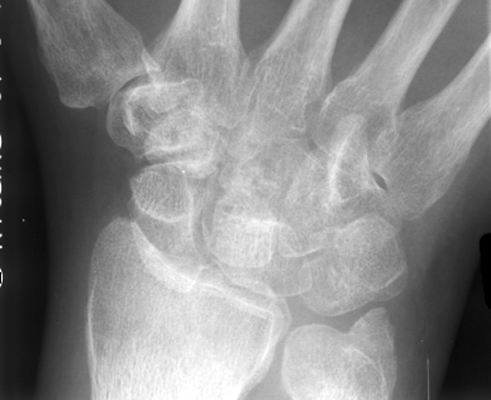

Frontal radiograph of the wrist reveals overlap of the distal carpal row with the proximal carpal row. This overriding gives rise to the "crowded carpal" appearance and is a sign specific for volar perilunate dislocation. It is secondary to proximal migration of the distal row of carpal bones during subluxation.

AP wrist - Click on the image for a larger version